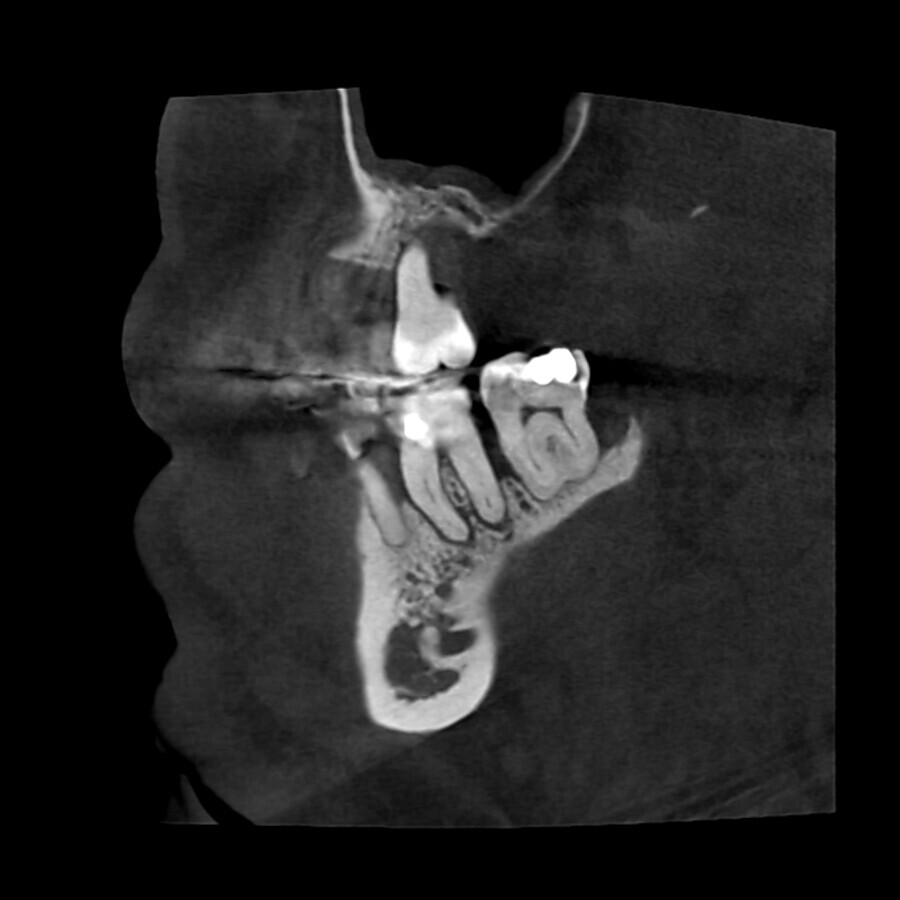

A revision treatment by Dr Silviu Bondari from Beuzeville in France also demonstrates that retreatment can be performed quickly and easily with the new endodontic motor. In a 30-year-old patient, removal of the insufficient gutta- percha filling also proved necessary owing to periapical periodontitis in tooth #36 (Fig. 4). At a speed of 1,000 rpm with continuous rotation, a delicate MicroMega Remover file was inserted to over two-thirds of the distal root canal length. The remainder of the root was then treated with a HyFlex EDM OneFile in the contra-angle handpiece at 500 rpm. HyFlex EDM files of size 20/.05 were used in the mesial root canals. The speed was also set at 500 rpm. The HyFlex EDM OneFile was then used in the mesial canals for final shaping of the root canal. A 40/.04 EDM file was used in the distal root canal. The result on the radiograph promised a more durable obturation than the initial treatment five years earlier (Figs. 5 & 6).